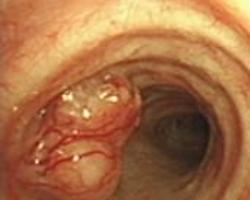

肿瘤多发生于腭弓、扁桃体、软腭缘、悬雍垂,其次见于软腭背面、下咽后壁、杓会厌襞等处。乳头状瘤外形不一,呈红色或灰白色,质较硬或软,瘤体多不大,有蒂或无蒂,单发或多发,为疣状、菜花状或颗粒状。在小儿可呈弥漫性、多发性。